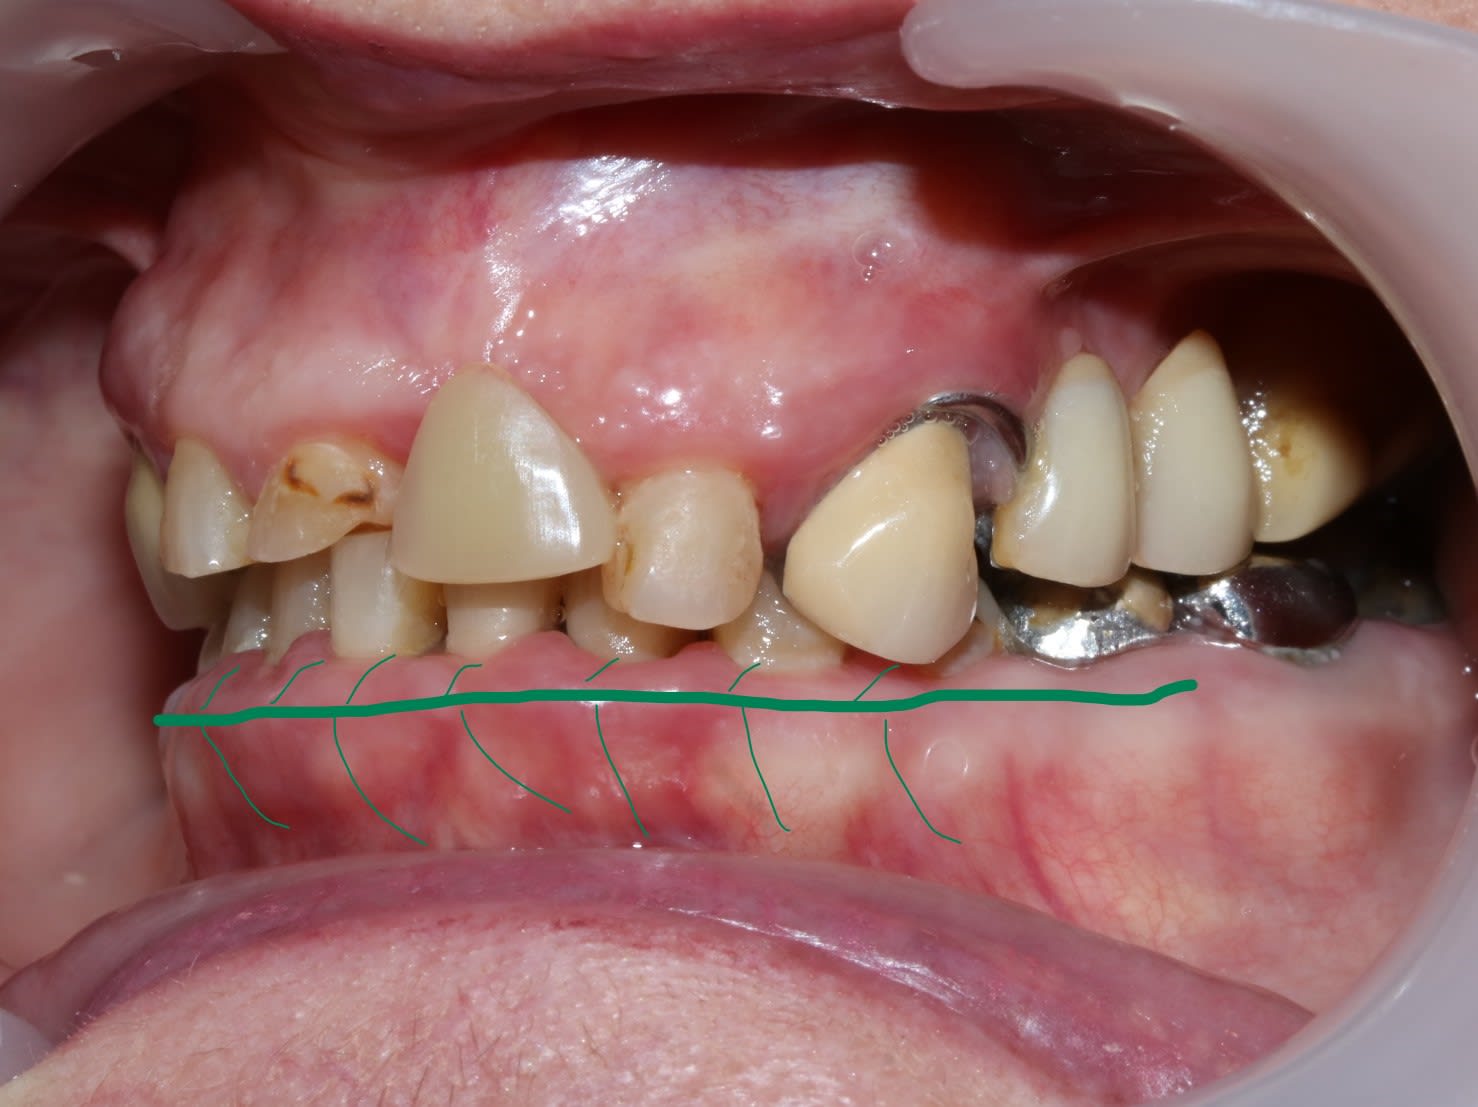

Bon , si tu ne regardes que la photo du bas :

tu as l impression que c est pas trop mal , hein?

et pourtant quand tu emboîtes le haut , ça s emboîte bien , mais tu vois bien que c est tout tordu qu il y a un truc qui ne va pas .

C est donc que le bas ne va pas non plus .donc faut couronner TOUTES les dents .

Pour le bas : à part de 33 à 43 tous le reste est sculpté de main de dentiste et prothésiste à la truelle. Donc .... j'ai pas confiance.

je pense que tout le monde a un peu raison .

Sethef a raison , la canine fait partie du debut du pb

Dant attend la photo de profil , ok aussi , il dit qu il n y a pas de baisse de dv , on va voir

Prunelle dit qu il refait d abord le bas qui va lui guider le haut , et c est pas con du tout .

et moi je pense à un truc qui peut réunir tout ça .

en regardant cette photo .

quand on voit cette ligne osseuse de plus grand contour , on se dit qu il y a eu une résorption osseuse horizontale du à un pb occluso paro .

mais si on y regarde mieux , on a l impression que cette crête est plus en avant que le surplomb des dents ant .

j ai comme l impression que c'était une classe 2 avec legere beance , qui par perte de calage post , que ce soit par perte des dents ou des protheses en sous occ ou meme la latero deviation de la canine ,aurait lingualé les incisives du bas et elles auraient reculé .

d où le recul des dents / à la crete osseuse .

ce qui voudrait dire que :

p'tre que la canine n etait pas trop grosse à l epoque , que le dentiste avait juste cherché à obtenir un contact palatin à l époque , et qu entre temps elle aurait eu une perte de dv par de multiples limages d équilibrations et par la vie tumultueuse .